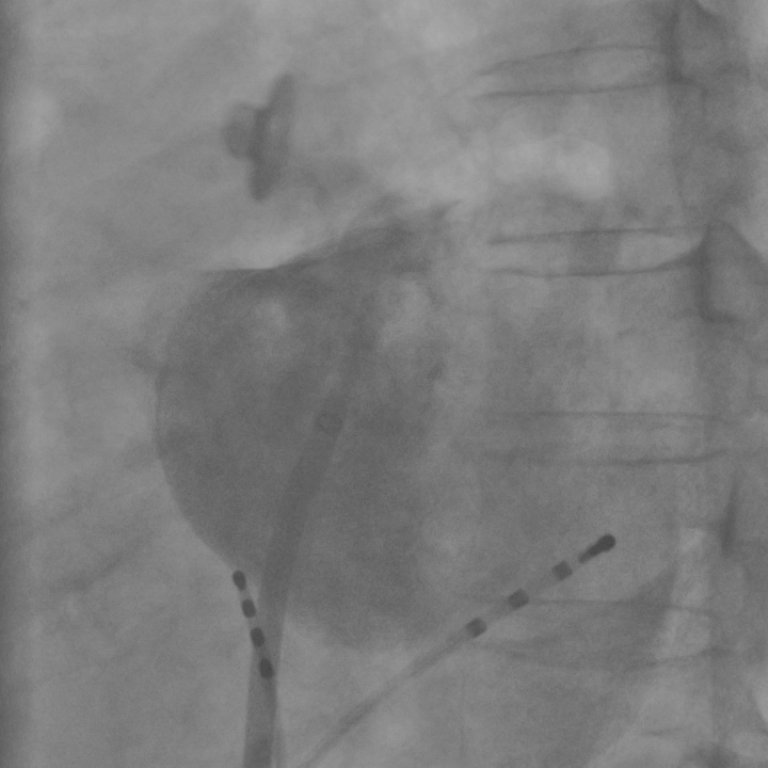

Refer to caption

Figure 4: (a) Contrasted fluoroscopic image. The registration result when using ρshadDSAsuperscriptsubscript𝜌shadDSA\rho_{\mathrm{shad}}^{\mathrm{DSA}} (b) had an error of 6.7 mm. By using ρCADEsubscript𝜌CADE\rho_{\mathrm{CADE}}+ρedgesubscript𝜌edge\rho_{\mathrm{edge}} (c), the left border of the LA model fits better to the left edge of the CA and the error reduced to 3.1 mm